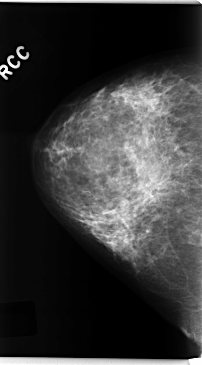

C_0222_1.RIGHT_CC

RIGHT_CC LINES 4744 PIXELS_PER_LINE 2624 BITS_PER_PIXEL 12 RESOLUTION 50 NON_OVERLAY